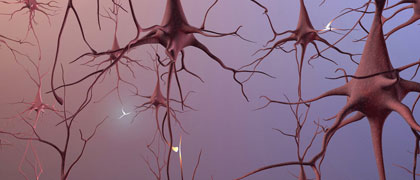

Jannis Productions. Rebekah Fredenburg, computer animation; Stacy Jannis, illustration/art direction.